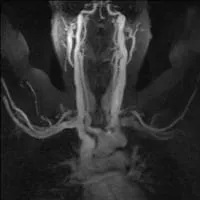

MR venography (MRV) can be performed in two ways. First is direct MRV. The physician injects contrast into a small arm vein. Shortly thereafter, the MRI scanner creates images as the contrast passes through the arm and chest. Direct MRV shows only veins, and only in one arm. In contrast is indirect MRV. Again, the physician injects contrast into a small arm vein. In contrast to direct MRV, scanning begins after a delay. First, injected contrast travels through the heart, the lungs, the arms, and returns through the arm veins. At this time, the MRI scanner creates images, showing both arteries and veins, in both arms. MRV shows the veins while eliminating other structures. MRV requires no radiation. If used in conjunction with MRI, superb soft tissue detail is available. Excellent depiction of fibrous bands, muscle anomalies, bones, and brachial plexus is possible with the combination of MRV and MRI.

This patient had an MR angiogram, followed by an MR venogram. Slide the handle side to side to see the difference between the two studies.